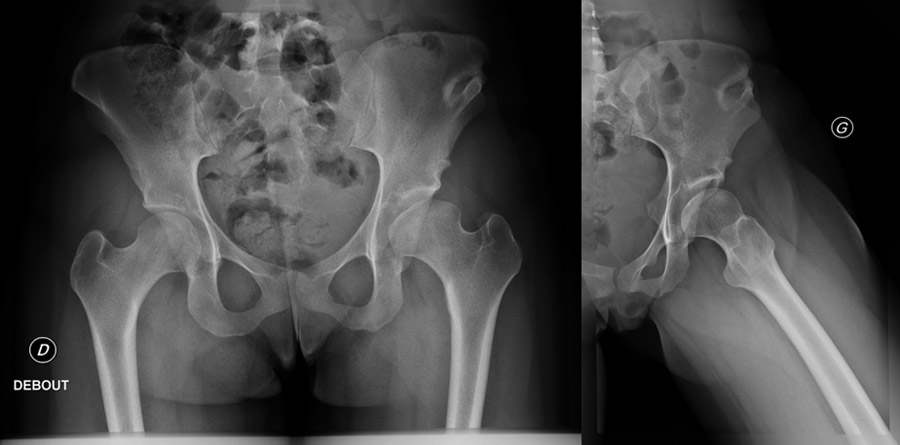

Current pre-op X-rays

Current pre-op X-rays: A total lysis of the shelf is observed